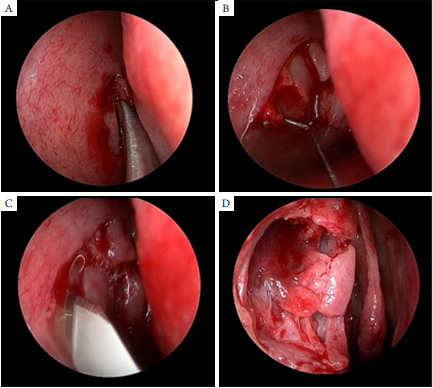

所有患者住院后均同一手术医生实施En-DCR。所有入组病例由一名独立的工作人员随机分为医用自交联透明质酸钠凝胶组(A组;千创复,常州百瑞吉生物医药有限公司)和对照组(B组),记录患者的年龄、性别、主诉、症状持续时间和预后。术后1、2周及1、3、6、12个月随访。A组在En-DCR术中使用医用自交联透明质酸钠凝胶填充鼻腔泪囊吻合口及其周围鼻腔黏膜,B组在En-DCR术中未使用医用自交联透明质酸钠凝胶填充鼻腔泪囊吻合口及其周围鼻腔黏膜。En-DCR的手术技术:患者取仰卧位,全身麻醉后进行手术。使用0°4mm鼻内窥镜(德国KarlStorz公司)直接观察,在泪囊窝区切开鼻外侧黏膜并移除(约1cm×1.2cm)(图1A),用金刚砂磨头(XPS3000,Medtronic)磨薄上颌骨额突骨质后再用咬骨钳咬除(图1B),形成约1cm×1.2cm大小骨窗暴露泪囊。经上泪点注入透明质酸钠(爱维,博士伦)撑起泪囊,用3.0mm刀(Beaver Visitec International)于近泪囊上缘处弧形切开泪囊内侧壁形成“C”形泪囊黏膜瓣(图1C),修剪泪囊黏膜瓣及鼻黏膜,使二者切缘对位贴合(图1D)。这是B组患者手术的最后一步。而在A组中则将医用自交联透明质酸钠凝胶填充于吻合口及周围粘膜处(图2,3)。术后予患者每天4次妥布霉素地塞米松眼药水(TobraDex,ALCON)点眼1周,后改为氧氟沙星滴眼液和普拉洛芬滴眼液均为每天4次,持续2个月,每日两次糠酸莫米松喷鼻剂喷鼻(Nasonex,MSD),持续3个月。术后48h观察鼻部及泪点处渗血情况,术后第3天行泪道冲洗及鼻内窥镜检查,术后2周仔细清除所有患者吻合口处的凝血块。术后2周、1个月、3个月、6个月、12个月复诊时均行泪道冲洗,鼻内镜检查评估伤口愈合情况(观察患者吻合口黏膜上皮化、瘢痕、肉芽肿及开放情况)。以上观察指标均一名独立的医生记录下来。

20230203160523_3026.png

图1 En-DCR手术步骤

Figure 1 Procedure of endonasal endoscopic dacryocystorhinostomy